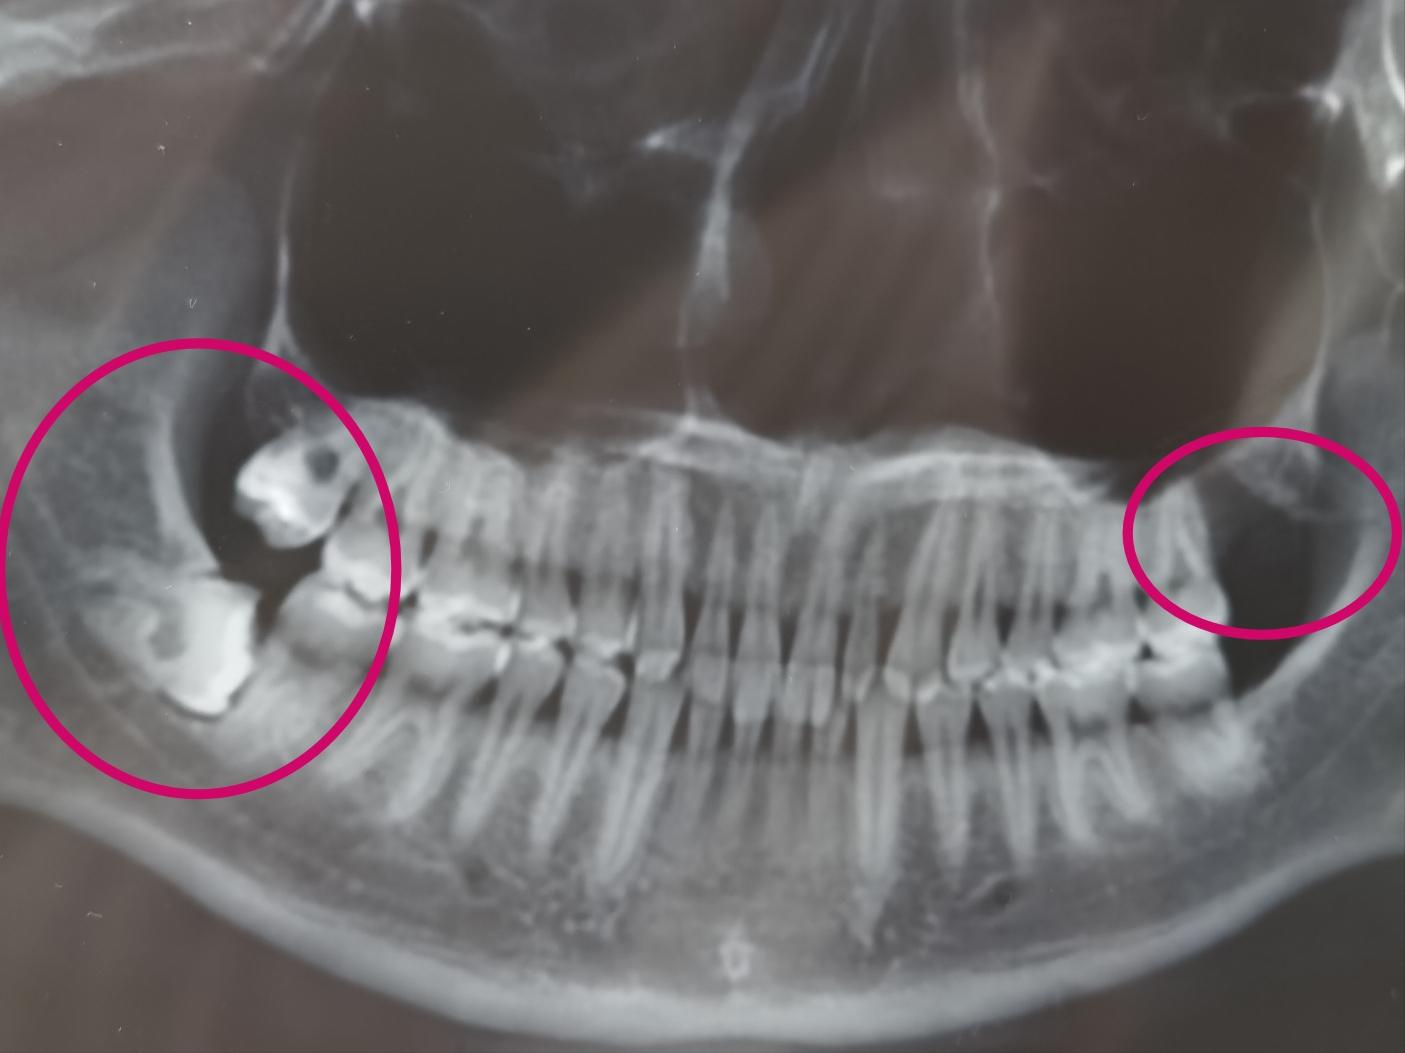

应该在第一次拔牙的时候顺便拍了,导致我又挂了第二趟专家号...下图是拔除1号牙但未拔除剩余智齿:

依稀可以看到1号齿的创口还留着坑慢慢长,牙齿也算伤筋动骨一百天,专家号的老医生看了看我的牙片,表示需要他谨慎的对待。1号牙一共打了1针麻药,2-3号一共打了我4针麻药,量太足劲太大,从嘴麻到脑子的感觉...

附上最后的拔完ct图: